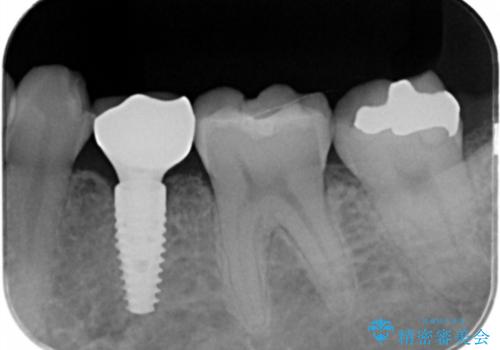

歯根が吸収し残すことのできない乳歯を抜去後、隣の歯を削らずに済むインプラント治療で咬合機能の回復を計画します。

乳歯の抜去後、インプラントを用いてしっかりと咬合機能を回復することができました。